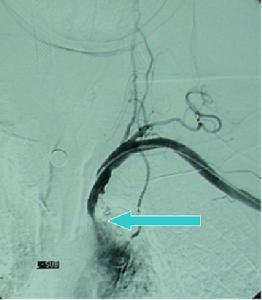

出血性腦梗死造影2、根據出血性腦梗死的發生時間分兩型

出血性腦梗死2、影像學檢查腦CT掃描或MRI檢查等影像學檢查提示出血性梗死。